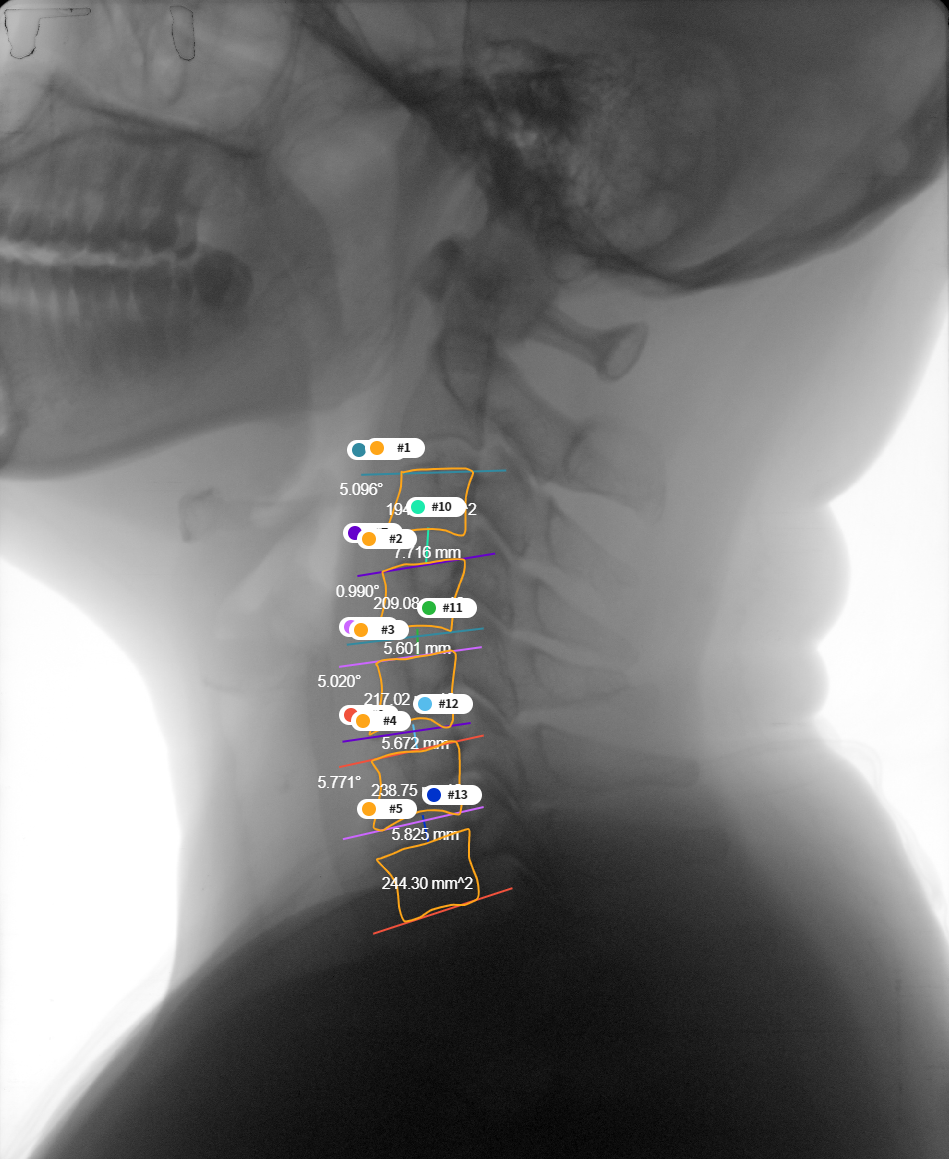

[요추 4, 5번 간의 디스크 높이 및 각도 측정]

- 데이터 종류 예시

대표도면 데이터 종류 예시 데이터 종류 경추x-ray 흉추 MRI 흉추CT 예시

데이터 구성 경추 디스크의 높이

경추 각 추체에 대한 bounding boxT2 axial image에서 흉추5-6번 구간의 면적

T2 axial image에서 척수 영역에 대한 외곽선흉추골화증평가

흉추골화증 병변에 대한 bounding box데이터 포맷 원본: dicom,

학습데이터: jpg

어노테이션: txt

ROI: JSON원본: dicom

대표도면 질환별 라벨링 예시 구분 X-ray MRI CT 퇴행성 경추협착증 (DCS)

데이터 포맷 dicom 포맷, json 포맷 dicom 포맷, json 포맷 dicom 포맷, json 포맷 대표도면 질환별 라벨링 예시 구분 MRI CT 흉추 척수증 (DTM)